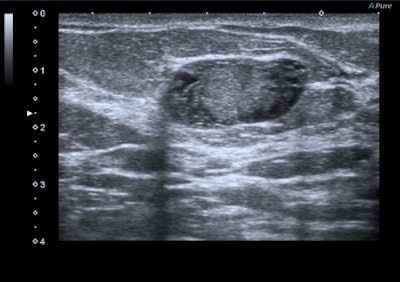

Elastography can add important details to define the epithelial and connective tissue components and their different elasticity even if the technique appears more useful in the study of focal pathologies, the authors wrote. Focal benign disease usually appears as hypoechoic (solid nodular disease) or anechoic areas, more often with regular shape and clear boundaries. These nodules are usually round or ovoid in shape with a "wider-than-tall" appearance indicating an orientation that is parallel to the chest wall.

"Ultrasound structure is often homogeneous with a large variability of echogenicity. Vascularization is variable and dependent on nodule histology," they stated. "Generally, benign lesions are harder than normal breast tissue but softer than malignant tumors. Exceptions can occur and some benign lesions, such as hyalinized fibroadenoma and fat necrosis, can be hard at palpation and can cause false positives at elastography examination."

Benign lesions are described at elastography as lesions with a low color map score (score 1-2), while the best cut-off point for discriminating benign from malignant masses falling at the 3-4 boundary of color map classification, according to the Ueno-Itoh score system. Cysts often appear as hard and low deformable lesions, commonly represented with a blue pattern at the color map and with a high strain ratio because of their low compressibility.